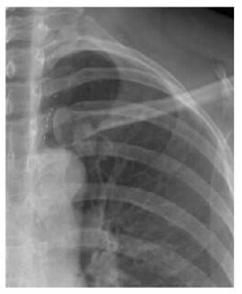

案例二:

圖二 左鎖骨重疊致密結節,誤為衣服紐扣,病理肺腺癌

案例解析:

該病例發生在國內某基層醫院,病患首先通過胸片攝影篩查,顯示出左上肺野內帶高密度橢圓形結節,由于形狀與紐扣極為相似,誤為衣服紐扣,并未做進一步診斷。第二年之后,病患再來復查,卻發現照片上結節影增大,立即進一步診斷檢查,最終經過活檢證實為肺癌,錯過了最佳的肺癌治療期。